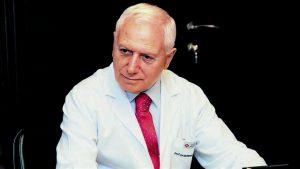

Οι ερευνητές, με επικεφαλής τη δρα Ελίζαμπεθ Όελσνερ, επίκουρη καθηγήτρια ιατρικής του Ιατρικού Κολλεγίου του Πανεπιστημίου Κολούμπια της Νέας Υόρκης, που έκαναν τη σχετική δημοσίευση στο περιοδικό πνευμονολογίας «The Lancet Respiratory Medicine», μελέτησαν στοιχεία για περισσότερους από 25.000 ανθρώπους, καπνιστές και μη.

Το κάπνισμα λίγων τσιγάρων καθημερινά είναι πολύ πιο επικίνδυνο από ό,τι νομίζουν πολλοί. Ο καθένας πρέπει να ενθαρρυνθεί σοβαρά να κόψει το κάπνισμα, άσχετα με το πόσα τσιγάρα καπνίζει τη μέρα», δήλωσε η δρ Όελσνερ.